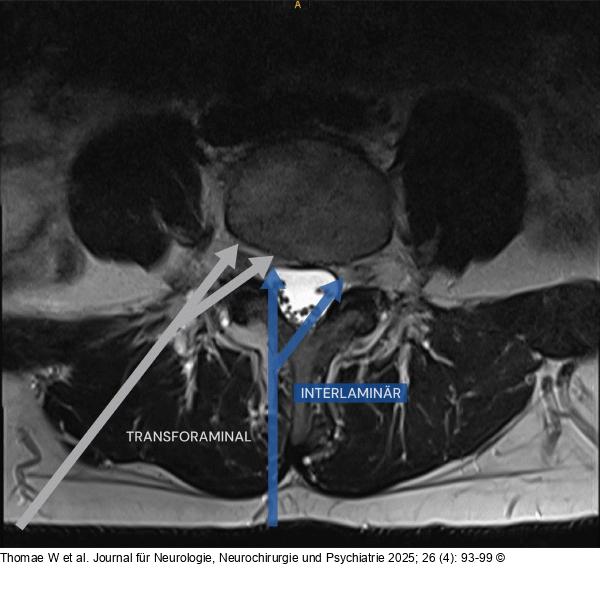

Abbildung 5: Zugangstrajektorie

Endoskopische Zugangstrajektorien der Lendenwirbelsäule: Die Abbildung illustriert die interlaminäre (blauer Pfeil) und transforaminäre (grauer Pfeil) endoskopische Zugangstrajektorie am Beispiel eines axialen T2-gewichteten MRI-Bildes der Lendenwirbelsäule. Der blaue Pfeil stellt den Zugang über das Interlaminärfenster dar, über welches ipsilateraler/kontralateraler Rezessus und zentraler Spinalkanal dekomprimiert werden können. Der graue Pfeil zeigt die transforaminäre Route zu extraforaminären, intraforaminären und intraspinalen Pathologien auf. Das chirurgische Risiko des interlaminären Zugangs der Brustwirbelsäule erhöht sich aufgrund der Lage des Rückenmarks deutlich, was die Anwendung im Bereich der Brustwirbelsäule limitiert. |